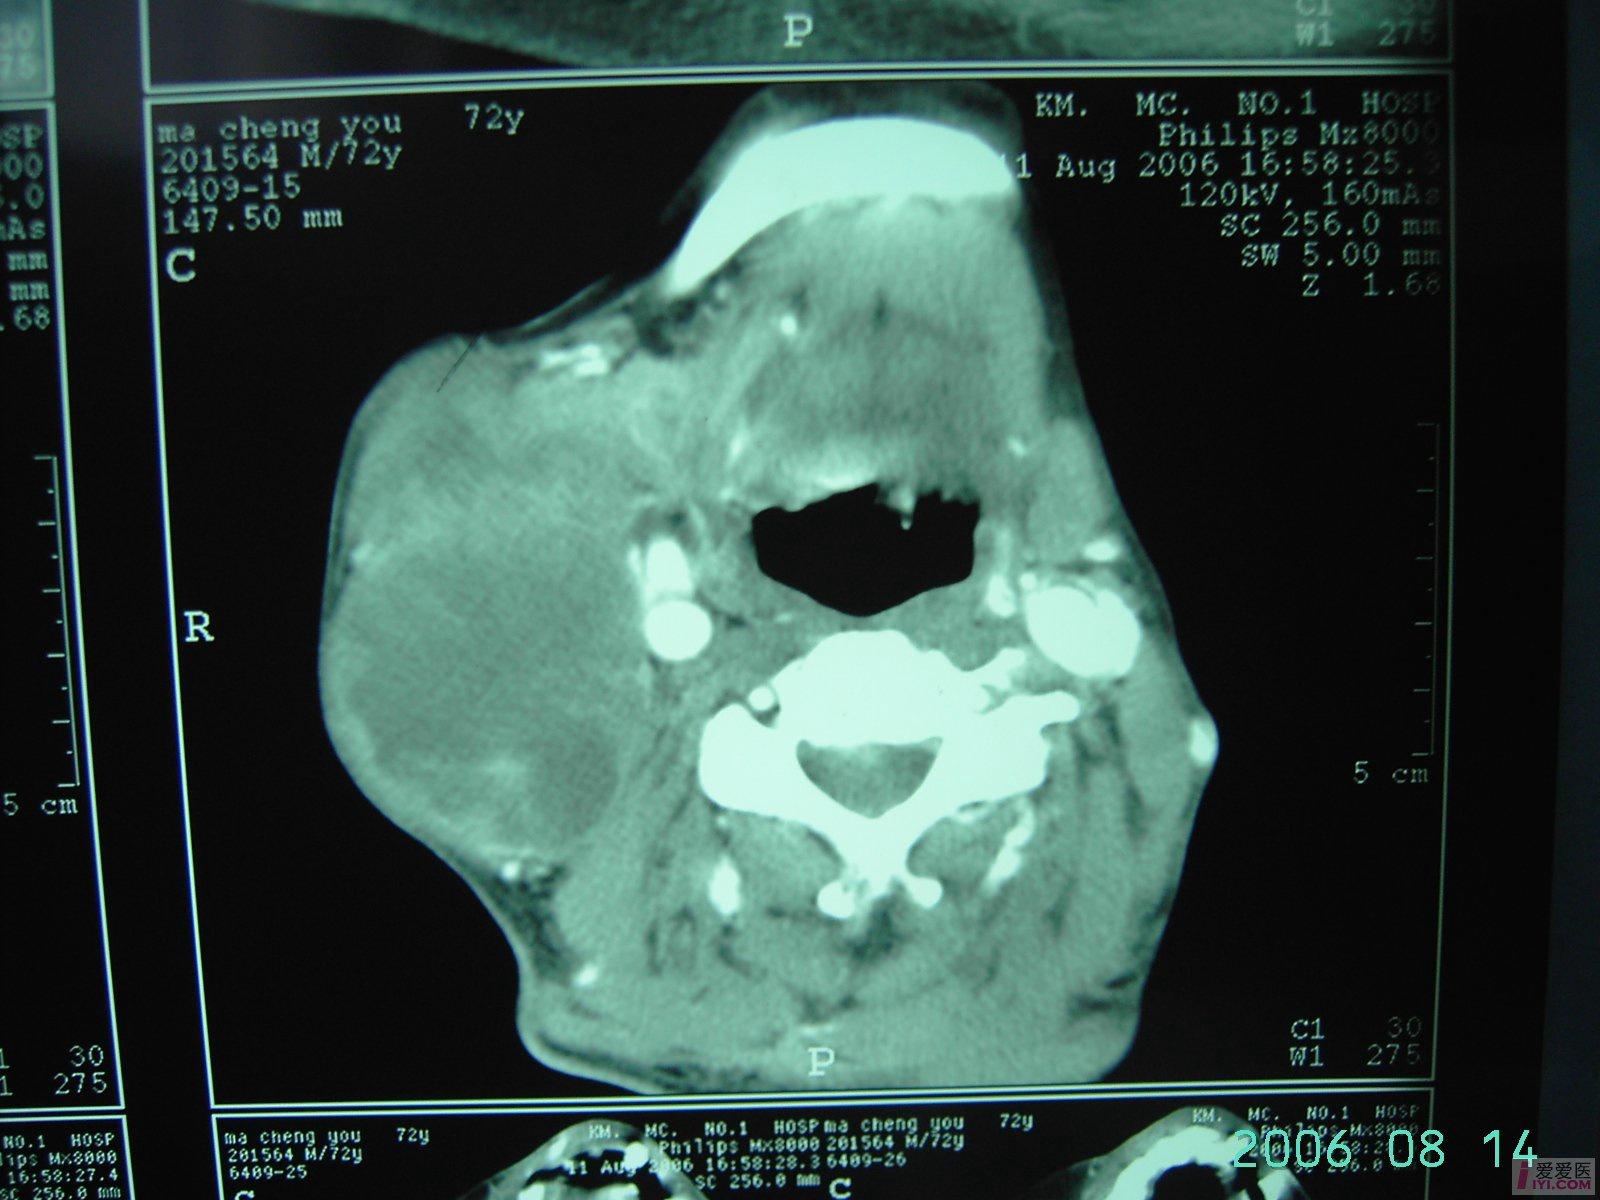

原创颈部恶性肿瘤晚期肺转移

图片尺寸1600x1200